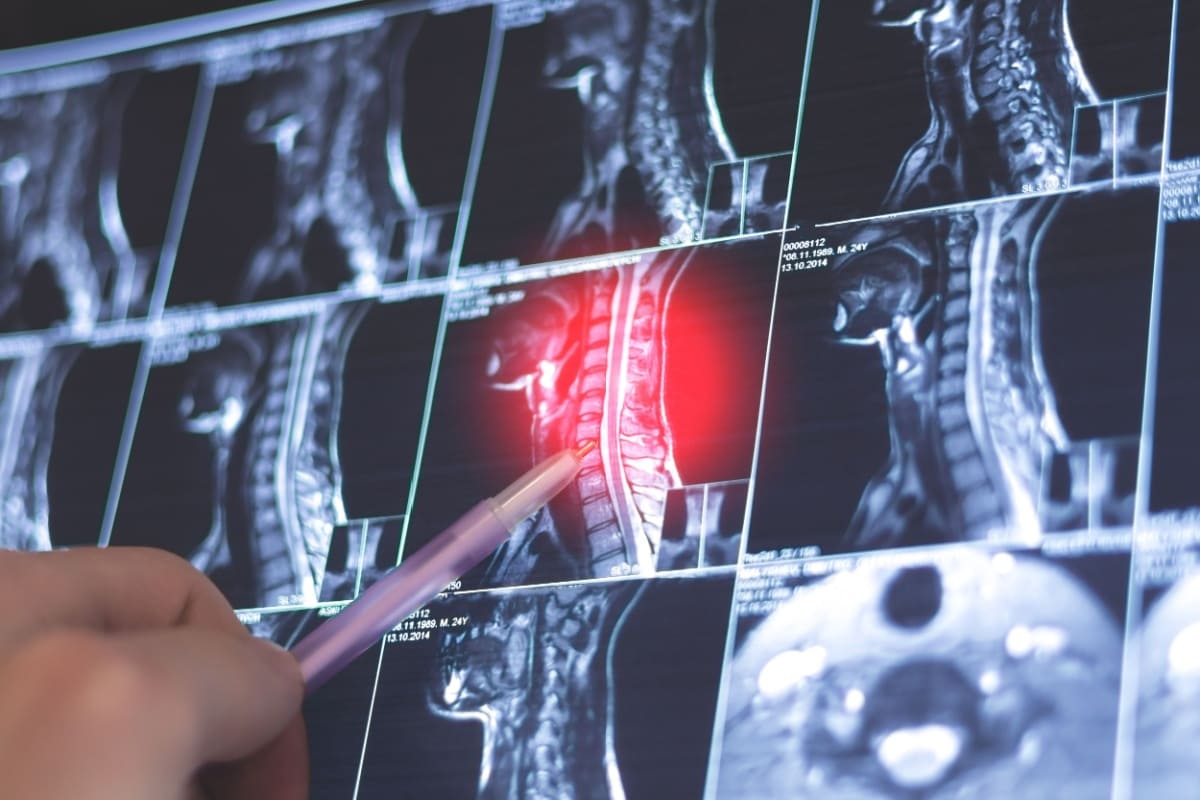

Rolul RMN în diagnosticul stenozei spinale

Imagistica prin rezonanță magnetică (RMN) joacă un rol esențial în diagnosticul stenozei spinale datorită capacității sale de a oferi imagini detaliate ale structurilor coloanei vertebrale și ale țesuturilor moi, cum ar fi măduva spinării și nervii. RMN-ul este preferat în acest context datorită nivelului său înalt de precizie și siguranță, fiind metoda de referință pentru evaluarea stenozei spinale și a altor afecțiuni ale coloanei vertebrale.

Procesul de scanare RMN implică aplicarea unui câmp magnetic puternic, care afectează protonii din corp. Aceștia emit semnale care sunt apoi preluate de dispozitivul RMN și transformate în imagini detaliate. În cazul coloanei vertebrale, acest proces permite obținerea unor imagini clare ale măduvei spinării, nervilor și discurilor intervertebrale, esențiale pentru evaluarea stenozei spinale [3].

Unul dintre principalele avantaje ale RMN-ului în diagnosticul stenozei spinale este capacitatea de a furniza imagini foarte detaliate ale structurilor moi ale coloanei vertebrale, cum sunt măduva spinării, nervii și discurile intervertebrale. Aceasta este o zonă pe care alte tehnici imagistice, cum ar fi radiografiile și tomografiile computerizate, nu o pot vizualiza la fel de detaliat.